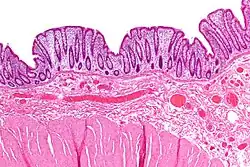

Rectal prolapse may be confused easily with prolapsing hemorrhoids.[5] Mucosal prolapse also differs from prolapsing (3rd or 4th degree) hemorrhoids, where there is a segmental prolapse of the hemorrhoidal tissues at the 3, 7 and 11 o'clock positions.[13] Mucosal prolapse can be differentiated from a full thickness external rectal prolapse (a complete rectal prolapse) by the orientation of the folds (furrows) in the prolapsed section. In full thickness rectal prolapse, these folds run circumferential. In mucosal prolapse, these folds are radially.[10] The folds in mucosal prolapse are usually associated with internal hemorrhoids. Furthermore, in rectal prolapse, there is a sulcus present between the prolapsed bowel and the anal verge, whereas in hemorrhoidal disease there is no sulcus.[3] Prolapsed, incarcerated hemorrhoids are extremely painful, whereas as long as a rectal prolapse is not strangulated, it gives little pain and is easy to reduce.[5]

Diagnosis

Mucosal prolapse can be differentiated from a full thickness external rectal prolapse (a complete rectal prolapse) by the orientation of the folds (furrows) in the prolapsed section. In full thickness rectal prolapse, these folds run circumferential. In mucosal prolapse, these folds are radially.[10] The folds in mucosal prolapse are usually associated with internal hemorrhoids.[21]